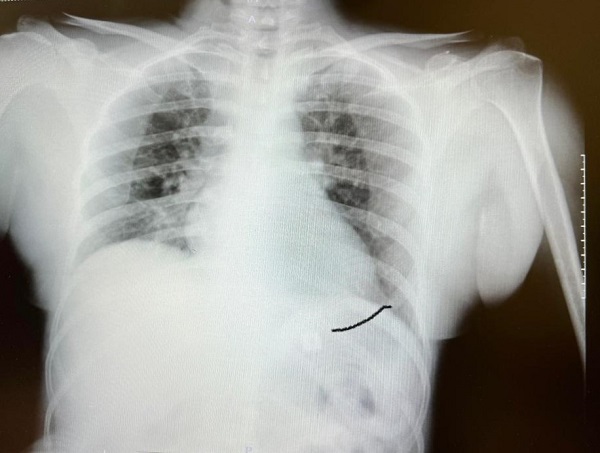

SANKO Üniversitesi Tıp Fakültesi Göğüs Cerrahisi Ana Bilim Dalı Başkanı Prof. Dr. Elbeyli, bilinci kapalı olarak hastaneye getirilen Sultan Tıraş’ın, ciddi ve hayatını kaybetme riski çok yüksek bir olay yaşadığını vurguladı. Sultan Tıraş’ın Gaziantep’te başka özel hastanede yapılan radyolojik tetkikler ve değerlendirmeler sonucu daha önce başka bir merkezde boyun omurlarına yerleştirilen metal disklerin yerinden oynadığının belirlendiğini hatırlatan Prof. Dr. Elbeyli, sözlerini şöyle sürdürdü: “O hastanede beyin ve sinir cerrahisi uzmanı tarafından ameliyata alınan Sultan Tıraş’ın boyun omuruna konulan iki aparattan biri çıkarılmış, ancak diğerinin yemek borusunu delip mideye indiği belirlenmiş. İlgili hekim bana ulaşarak bilgilendirmeyi yaptı ve hastayı hastanemize sevk etti. Yoğun bakıma alınan hastaya yaptığımız detaylı tetkikler ve klinik değerlendirme sonucu mediyastenit (ciddi göğüs enfeksiyonu) belirlendi. Bu ciddi bir sorun olup, hayati riski yüksektir. En hızlı şekilde tıbbi tedaviye başladık, gastroenteroloji bölümümüzde endoskopi yapıldı. Yemek borusunda oluşan delik ve delikten mideye inen metalik cerrahi aparat görüldü. Göğüs kafesi içinde ciddi bir iltihap ve hava birikimi vardı. Hasta yakınları durum ile ilgili bilgilendirildi, riskler kendileri ile paylaşılarak hastamıza tıbbi müdahale edebilmemiz gerekli onayları alındı.”

“Yaklaşık 6 saat süren bir ameliyat oldu. Hastamıza ilk endoskopik yol ile göğüs orta bölümdeki (mediasten ki bu bölgeye insan hayatının makine dairesi deriz) cerahat boşaltılıp tahliye edildi. Daha sonra boyun bölgesindeki biriken iltihap temizlendi. Yemek borundaki 2 cm’lik perforasyon (delik) tespiti ve tamiri yapıldı” diyen Prof. Dr. Elbeyli, şu bilgileri paylaştı: “Hastamız ameliyat sonrası bir süre yoğun bakımda, daha sonra serviste izlendi ve tedavi sonrası şifa ile taburcu edildi. Hastamızın yaşadığı bu durum, tıp literatüründe ender görülen bir olay olup ciddi ve yüksek hayati riski içerir. Sultan Hanımın sağlığına kavuşmasında emeği geçen herkesi kutluyorum.” Prof. Dr. Elbeyli, “Bu şehre ve dolayısıyla bölgeye böyle bir hastane kazandırdıkları için SANKO Ailesine teşekkür ederim. Ülkemizin sınıf atladığı alanlardan biri de sağlıktır. Bölgenin gözbebeği olan hastanemiz, kurucusundan hekimlerine, yönetiminden idari çalışanlarına kadar en iyisini sunmak için azami çaba gösteriyoruz” diyerek sözlerini tamamladı.

SANKO Üniversitesi Tıp Fakültesi İç Hastalıkları Ana Bilim Dalı Gastroenteroloji Bölümü Öğr. Üyesi Doç. Dr. Nimet Yılmaz, hastanın yutma güçlüğü ve nefes alamama şikayetleri nedeniyle SANKO Üniversitesi Hastanesi Göğüs Cerrahisi Bölümü’nden yönlendirildiğini bildirdi. Hastanın şikayetleri üzerine endoskopi (cerrahi müdahale olmaksızın sindirim sistemini incelemek amacıyla hastanın ağızdan girilmesi şeklinde yapılan işlem) yaptıklarını anlatan Doç. Dr. Yılmaz, şu bilgileri aktardı: “Endoskopi sırasında hastanın midesinde metalik bir oluşuma benzer yabancı cisim ile yemek borusunda ülser görünümü izledik. Lezyon bölgesi belirlendikten sonra hastamızın tedavisi için Göğüs Cerrahisi Bölümümüze durumu ilettik. Prof. Dr. Levent Elbeyli Hocamız hastamızın sağlığına kavuşması için gerekli tedaviyi planlayarak, başarılı bir operasyonla sonuca ulaştı. Emeği geçen herkese teşekkür ediyorum. Hastamızı sağlıklı bir ömür diliyorum.”